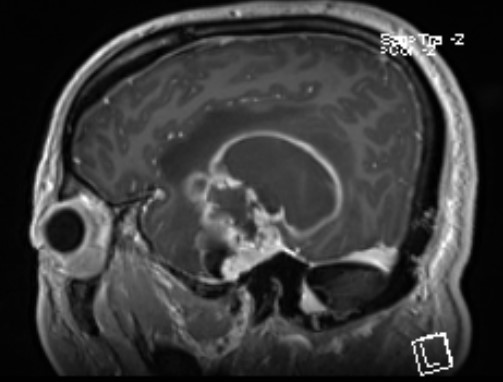

头部MR提示:右颞叶,岛叶及基底节区巨大占位,胶质母细胞瘤可能性大

矢状位

术前导航提示肿瘤与锥体束毗邻